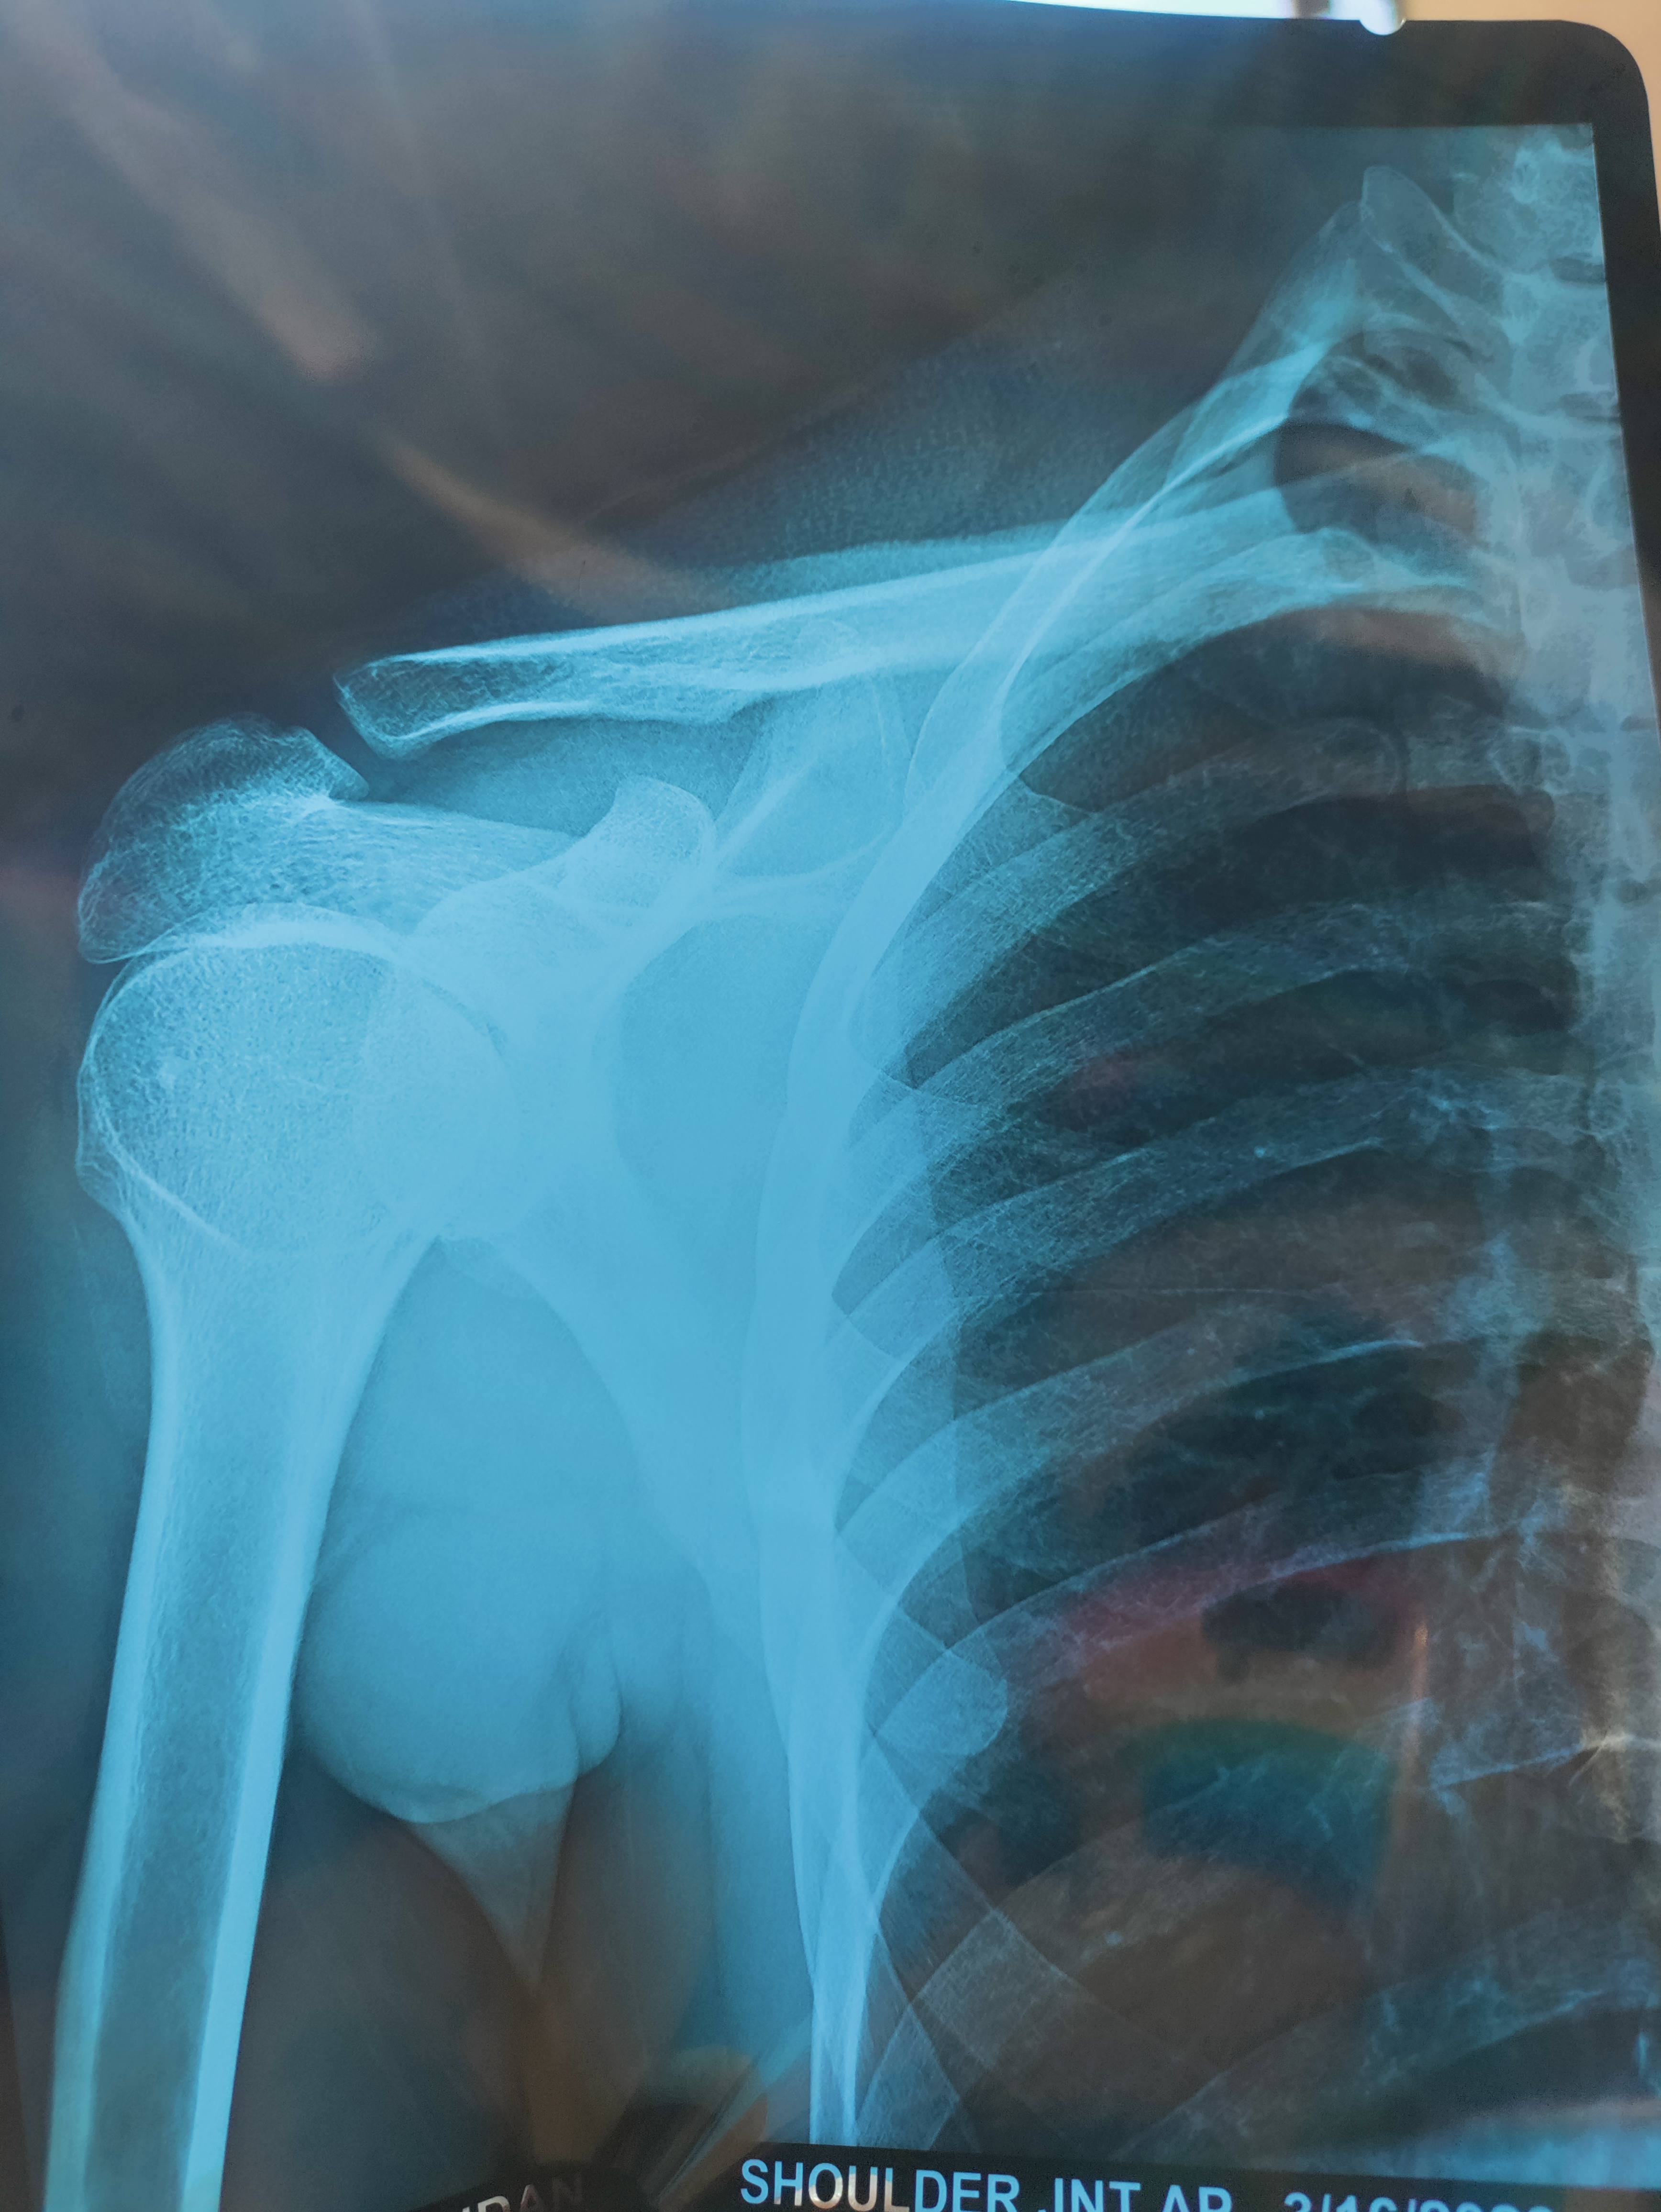

Sir accident ke baad 10 din patte lagaye hue the uske baad ka x-ray hain hath upar krne par dard ho raha hain kya opinion hain sir plzzz bataiye